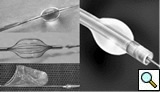

Similar to the native coronary, a 0.014 inch wire is usually used for balloon angioplasty or stenting. If the stent can not be advanced using a soft wire, the wire could be exchanged over the balloon to a stiffer wire or the second wire could be advanced and used as a body wire for a better support. If possible, filter wires or other protection devices should be used in all vein graft interventions [(Figure 2, see no-reflow chapter for details. Most commonly used work horse wires are balanced mid weight (BMW Boston Scientific), all track wire (ATW Cordis) or Prowater (Abbott Vascular)]. In the tortuous vessels, it may be necessary to exchange the wire over a balloon to a stiffer wire such as platinum plus or an iron man. Additional wire for support so called” body wire” can be utilized to improve stent delivery in tortuous vessels. Similar to the native coronary angioplasty, wire with stiffer or/and hydrophilic tips can be used for crossing a high-grade lesion such as PT choice, grand slam, PT2 wires, etc. However, these wires can easily enter a false lumen causing dissection or perforation. It is advised to exchange these wires with a softer tip wire once the lesion is crossed successfully to prevent distal vessel perforation.

One of the most common complication of PCI during vein graft interventions is the occurrence of “no-reflow.” After angioplasty or stenting of a vein graft, sudden cession of the distal flow could occur. This phenomenon thought to be secondary to distal embolization and platelet aggregation [2-4]. It can cause myocardial infarction, arrhythmias, hemodynamic collapse and death. It is usually treated with intra-coronary infusion of adenosine, calcium channel blockers, or nitroprusside [5-9]. After aggressive pharmacological treatment, it is usually reversible but it can be refractory causing severe myocardial damage and infarction. It usually occurs in old degenerative vein grafts or in thrombus containing lesions. However, based on the angiographic appearance, it is hard to predict which vessel is proned to this complication. There are few strategies developed in order to prevent this complication. Intra-venous glycoprotein IIb/IIIa inhibitors, which are very potent platelet aggregation inhibitors, despite success in the native coronary interventions have failed to decrease this complication in vein grafts PCI [10, 11]. On the other hand, distal filter devices have shown to significantly reduce the occurrence of this complication in vein grafts and should be routinely used if technically feasible [12-14]. A major limitation of distal filter devices is the absence of large distal vessels that can accommodate these devices and difficulty to advance such a bulky device across a high-grade lesion or across a tortuous vein graft. A recently approved proximal occlusion device has similar efficacy for the prevention of no-reflow in vein graft interventions [15]. By occluding the vein graft proximally during balloon angioplasty or stenting, flow can be stopped during stent expansion and atherosclerotic and thrombotic debris can be suctioned before the vein graft flow is restored preventing distal embolization. This technique requires lesions that are distal to the ostial vein graft and add substantial complexity and time to the procedure. Figure 2 shows the most commonly used protection devices for vein graft interventions.